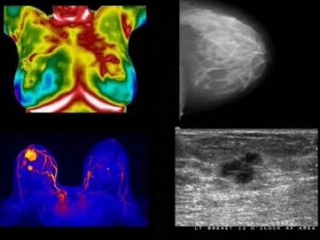

Alors que la mammographie, l’IRM ou l’ultrason visent à détecter une maladie déjà existante, la thermographie permet de mettre en évidence un problème, une situation à risque bien avant ce stade.

Elle ne se substitue pas pour autant aux autres formes de dépistage clinique. Mais lors d’une pathologie avérée, la thermographie permet encore de suivre l’évolution du traitement, de juger de son efficacité, en complétant idéalement la panoplie d’examens structurels adéquats. Votre médecin traitant ou thérapeute appréciera ce complément de diagnostic.